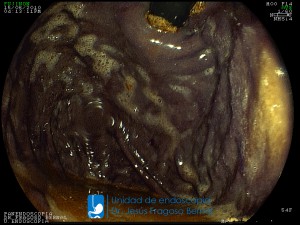

La Unidad de Endoscopía fue creada en 2002 por el Dr. Jesús Fragoso Bernal, es pionera en el estado por la utilización de la tecnología más avanzada, que nos permite ofrecer servicios integrales de diagnóstico y tratamiento para las enfermedades del aparato digestivo.

"La Unidad de Endoscopía se ha caracterizado por un progreso continuo desde su inicio marcando la pauta en los procedimientos endoscópicos en el estado de Tlaxcala y estando siempre a la vanguardia tecnológica."